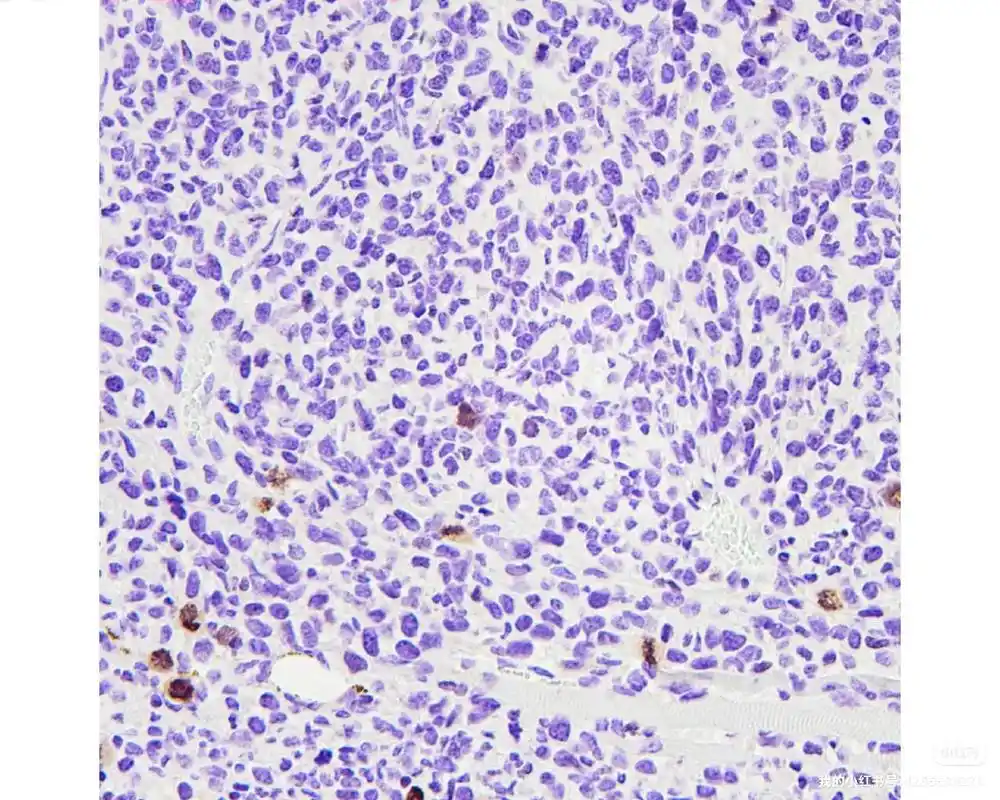

病理科主要通过制病理切片完成免疫组化实验来诊断疾病。用来制作病理切片的组织样有括宫颈、痰、胸腹水及尿液等。病理切片有石蜡切片和冰冻切片两种,常见的是石蜡切片。1 取材、固定:获取的组织样本经离心等处理后···